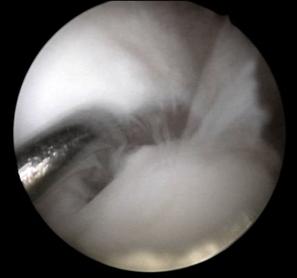

|

Fig. 1.15 Imagini artroscopice - osteocondrita disecanta: in stinga fragment condral partial detasat , in dreapta patul osos ramas dupa indepartarea fragmentului osteocondral detasat, se observa ca leziunea condrala este mai extinsa decit cea osoasa |